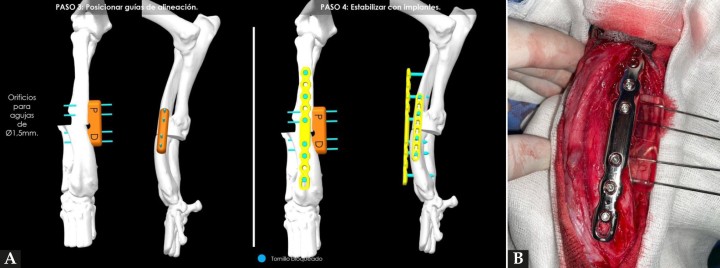

(A) Reproducción en 3D de la aplicación de la guía de alineación para mantener la fijación de los huesos mientras se coloca la placa principal. (B) Aspecto de la placa puente recién colocada junto a la guía de alineación.

Figura 4

Tras exponer el radio, el primer paso consistió en posicionar la guía de corte en la zona cráneo/medial del área media/distal de este hueso (según lo planificado), fijando temporalmente su posición con la ayuda de 4 agujas introducidas a través de los orificios proximales y distales de la guía. Una vez fijada, se realizaron los cortes con una sierra oscilante recta a través de las dos ranuras del dispositivo (Fig. 3B). A continuación, en un segundo paso, se retiró la guía de corte y se sustituyó por la de alineación, empleando el mismo sistema de fijación con agujas para conseguir la reducción de los fragmentos, según la planificación prevista. Esta segunda guía está diseñada para poder mantener en la posición adecuada los fragmentos mientras se estabilizan con la placa principal (Fig. 4A). En este caso, se colocó en primer lugar y como principal una placa bloqueada tipo puente que aplicamos sobre el área craneal del radio, con tornillos de 3,5 mm de diámetro (Fig. 4B). Posteriormente, colocamos otra placa de bloqueo auxiliar, de tipo multiorificios por el aspecto medial, con tornillos de 2,7 mm de diámetro para reforzar la estabilización.